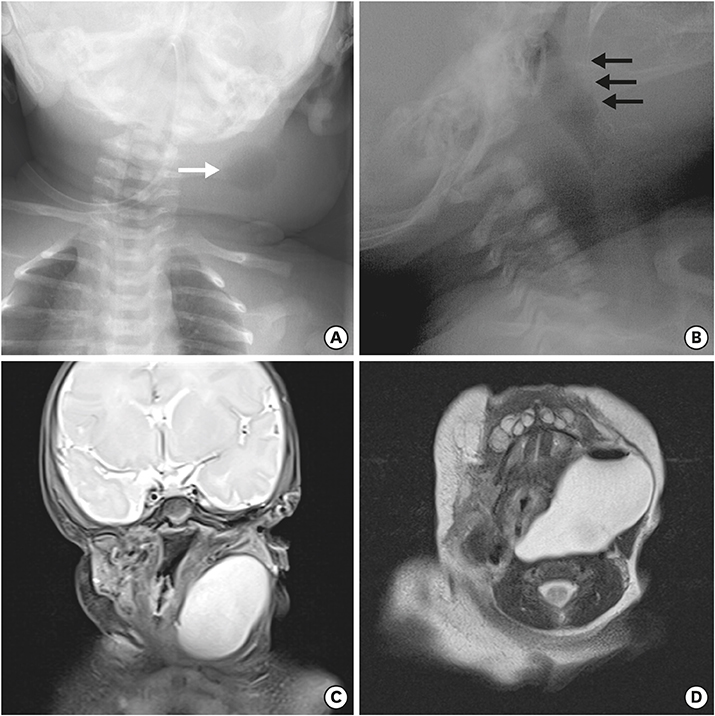

Fig. 3

(A) Neck anteroposterior view and (C, D) T2-weighted neck magnetic resonance imaging of cystic mass with air (white arrow). (B) Fistulography shows a faintly opacified hairline tract (black arrows) originating from the left pyriform sinus.

A newborn female infant, gestational age of 39+2 weeks, and 3.46 kg at birth was referred to our NICU due to a 7 cm sized left neck mass presented at birth. No significant medical history during antenatal care was noted. The baby arrived at our NICU 3 hours after birth and physical examination revealed a soft, tense, movable 7 cm long mass without signs of inflammation. Initial neck X-ray showed a 4.7×3.9 cm sized soft tissue density mass at left side of the neck containing round air density (Fig. 3A). With experience of patients with pyriform sinus cysts, gastric tube feeding was initiated from day 1. A sonographic study of the neck mass revealed findings consistent with pyriform sinus cyst, located at the medial side of the left carotid artery and extending to the posterior aspect of the left thyroid gland. The cyst was unilocular and contained isoechogenic debris. Esophagography showed a small tubular opacity from the left pyriform sinus adjacent to the air-filled cyst, suggesting a fistula (Fig. 3B). On neck magnetic resonance imaging (MRI), the fistula was not visualized but a cyst of homogeneous signal intensity without wall thickening or enhancement was visualized with air-fluid level, suggesting communication with the esophagus (Fig. 3C and D). On the 6th day of admission, pyriform sinus cyst resection and fistula ligation was done (Fig. 4). The size of the cyst was 7.0×3.5 cm on operation findings. Histological results of the dissected cyst were negative for malignancy and showed many benign squamous epithelial cells with some multinucleated histiocytes and mixed inflammatory cells. There was no intra-operative complication and the patient recovered uneventfully. Bottle feeding was initiated on postoperative day 7 and the patient was discharged 10 days after surgery.